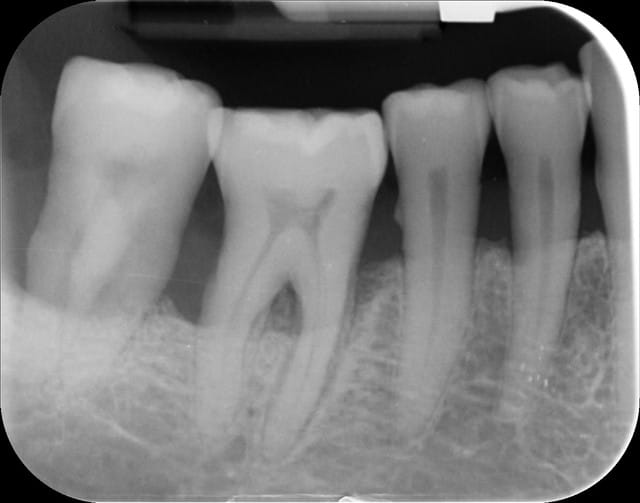

je fais bilan RA et

-sectR IV :46+ 47 sont à mon avis sur le bonus, mobilité III pr 47 , 46 presque pas mobile. (patient mastique dessus sans soucis, ne se plaint de rien)

-secteur III -edentement non compensé à partir de la 35

maxillaire: denté jusqu'au 6 comprises.

Je voudrais faire une PAP stellite remplaçant les dents du secteur III+ incisives manquantes et la question est quel compromis faire pour une prothese qui va durer